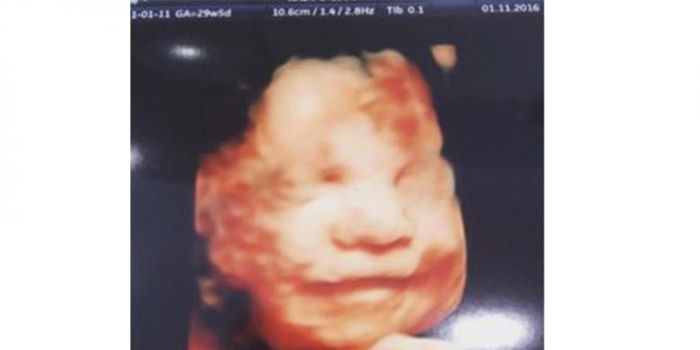

Aimee Fagan (27) seorang ibu asal Inggris mendapati kejutan luar biasa saat USG 4 dimensi. Ia melihat sendiri bagaimana janin tersenyum sangat lebar saat USG sedang berlangsung!

Janin tersebut tidak lain adalah calon anak ketiganya yang kini berusia 30 minggu.

Mendapati janinnya sadar kamera, Fagan sangat senang dan mengabadikan foto USG janin tersenyum tersebut.

Awalnya, saat USG baru dimulai, suster kesulitan menemukan wajah dari janin yang diprediksi berjenis kelamin perempuan tersebut.

Namun kemudian Mollie mengajak berbicara adiknya yang di dalam perut dan perlahan, janin tersebut bergerak dan memperlihatkan wajahnya.

Tidak berhenti sampai situ, Mollie terus mengajak bicara adiknya dengan celotehan khas anak kecil dan perlahan janin dalam perut ibunya tersenyum lebar!

“Perawat USG mengatakan bahwa dia tidak pernah melihat janin tersenyum begitu sering dan terlihat bahagia,” ujar Fagan.

Awalnya, ia dan perawat menduga itu hanyalah sebuah kebetulah biasa.

Namun ketika Mollie berhenti berbicara, janin tersebut tidak lagi tersenyum dan kembali tersenyum saat Mollie mkembali mengajaknya berceloteh.

“Seolah janinku mendengar dan menyukai kehadiran kakaknya,” imbuhnya.